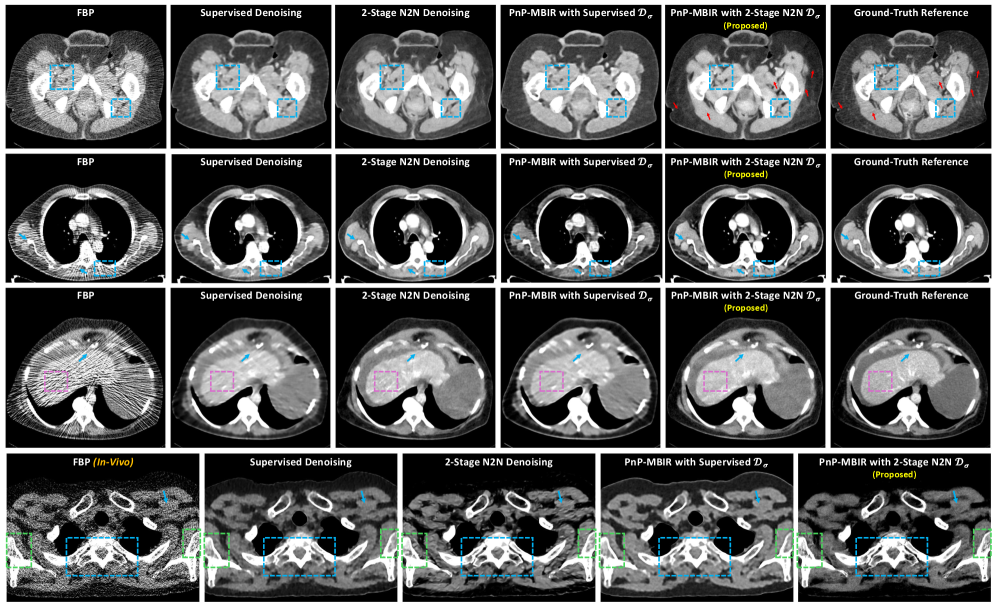

Fig. 1 qualitativly compares the reconstructions from FBP, supervised denoising, 2-stage N2N denoising, PnP-MBIR with a supervised prior, and our proposed PnP-MBIR with 2-stage (N2N) denoiser for dose-levels 100 mA, 70 mA and 40 mA respectively in the top, second and third rows. Finally a in-vivo data, acquired with 55 mA and 100 kVp, are presented in the bottom row. As expected, the low-dose FBP images (left column) are severely degraded by noise and streak artifacts. The standalone supervised denoiser (column 2) removes most of the random noise but leaves substantial structured streak artifacts and creates distortion and anomalies in the underlying anatomical structure (see blue arrows and blue boxes), since conventional supervised training framework cannot effectively learn to remove correlated streaks and noise. The standalone 2-stage N2N denoiser (column 3) further suppresses structured artifacts, but it introduces noticeable blurring and loss of fine details (see blue arrows and blue boxes). PnP reconstruction using the supervised denoiser as a prior (column 4) improves on image-domain denoising – some low-contrast features become clearer – but still leaves visible correlated artifacts in complex regions (e.g. liver, inter-tissue edges), resulting distorted reconstructions (magenta box) and loss of fine details (blue box). In contrast, the proposed PnP-MBIR reconstruction with the 2-stage N2N denoiser (column 5) yields the best visual quality: streaks and structured noise are substantially removed while high-frequency anatomical details (highlighted by blue boxes and arrows) are preserved. This output closely matches the ultra-high-dose reference (column 6) and, in practice, even exceeds it by eliminating subtle artifacts present in the ground truth reference (red arrows) due to photon starvation and attenuation in dense bone regions. A similar pattern holds in-vivo (bottom row): our method retains sharp bone edges and soft-tissue contrast (blue box and arrow) far better than other low-dose methods. In addition to noise and artifact reduction, our method maintains the subtle contrast between soft and hard bone tissues, ensuring better visualization of intra-bone structures (green boxes). Additional zoomed-in sections of the reconstructed images are provided in Appendix C for a comprehensive visual analysis.

Figs. 3–5 present zoomed-in sections from the reconstructed images obtained using different methods for qualitative evaluation. From the regions highlighted in Figs. 3–4, it is evident that our proposed PnP-MBIR reconstruction with the 2-stage N2N denoiser delivers superior visual quality. Specifically, streak artifacts and structured noise are significantly suppressed, while high-frequency anatomical details—indicated by green arrows—are well preserved. The resulting image closely approximates the ultra-high-dose reference, demonstrating the effectiveness of our approach. A similar trend is observed in the in-vivo results shown in Fig. 5 (zoomed-in red, blue, and yellow regions). Our method maintains sharp bone edges and soft-tissue contrast (blue and yellow sections) far better than competing low-dose reconstruction techniques. Beyond noise and artifact reduction, the proposed approach preserves subtle contrast between soft and hard bone tissues, enabling improved visualization of intra-bone structures (highlighted by green arrows).